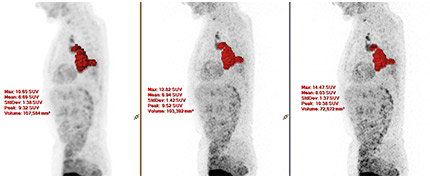

Bei einer Ganzkörper-Patientenstudie durch Forscher am Universitätsklinikum Salzburg in Österreich war mit ×Sharp eine verbesserte Darstellung kleiner Läsionen möglich. Die Anwendung von ×Sharp resultierte in einem höheren SUVmax im Vergleich zu Scans ohne ×Sharp. Die Größe der Läsionen lag im Bereich von 12 bis 20 mm.

Bild mit freundlicher Genehmigung des Universitätsklinikums Salzburg, Österreich